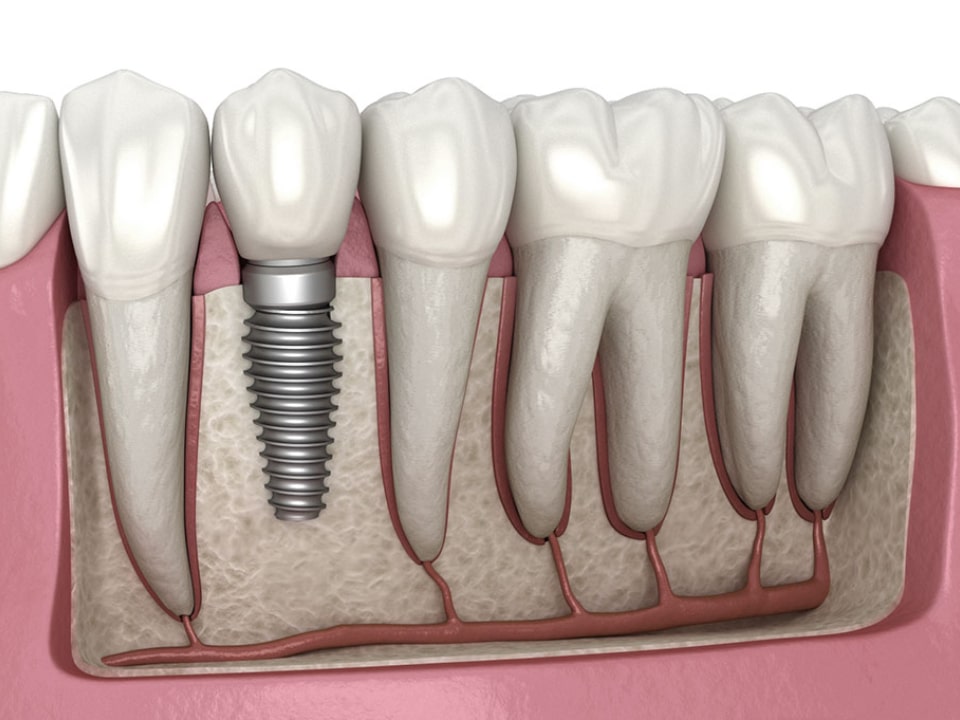

It is an artificial tooth root placed in the jawbone of the person in order to restore the function and appearance of the teeth with the right implant selection.

Since the implants fuse with your jawbone, they are permanent and you do not have to deal with constantly removing and replacing the prosthesis.